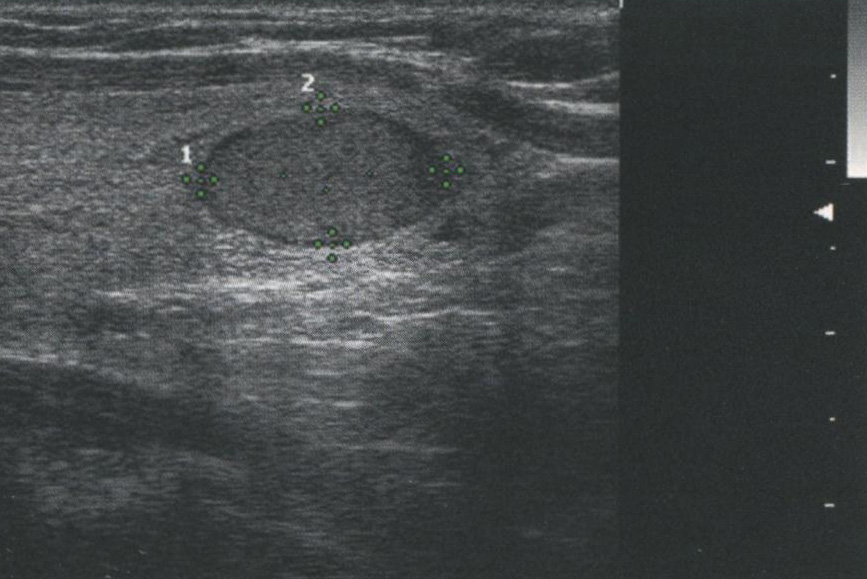

Однако усиление сигнала происходит не только при наличии кистозных узлов. Любая структура, вызывающая минимальное затухание УЗ-сигнала, будет иметь усиление кзади от себя. На рис. 2.13 продемонстрировано усиление сигнала кзади от солидной аденомы ПЩЖ. На рис. 2.14 показано усиление сигнала позади доброкачественного коллоидного узла. Из-за высокого содержания жидкости и коллоида в узле и, как следствие, уменьшения клеточного компонента затухание сигнала в этом образовании происходит в меньшей степени, чем в окружающей ткани щитовидной железы.

Рис. 2.14. Усиление сигнала. Этот доброкачественный коллоидный узел содержит много жидкости и коллоида, что приводит к уменьшению клеточного компонента. Сниженное затухание сигнала в узле обусловливает усиление сигнала, несмотря на то что этот узел является солидным